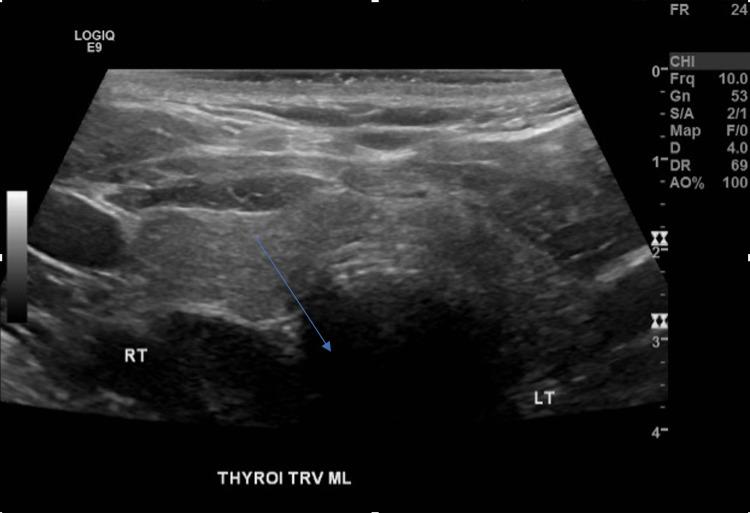

Parathyroid adenomas rarely weigh more than 4 grams. Our patient had a 5.3-gram adenoma causing bilateral knee pain limiting mobility, constipation, low back pain, and frontal headache. Presenting with calcium of greater than 17 mg/dl, the patient was treated with two rounds of hemodialysis, calcitonin, Zoledronate, and aggressive IV hydration to decrease calcium levels before parathyroidectomy. The patient then went on to develop the hungry bone syndrome, which was treated with calcium carbonate and calcitriol. This rare giant parathyroid adenoma presents a unique opportunity to learn about the pathogenesis and treatment of longstanding hyperparathyroidism causing hypercalcemia-associated symptoms and hungry bone syndrome after parathyroidectomy.

甲状旁腺腺瘤很少超过4克重。我们的患者有一个5.3克的腺瘤,导致双侧膝关节疼痛,限制了活动能力,还有便秘、腰痛和前额头痛。患者血钙高于17mg/dl,在甲状旁腺切除术前接受了两轮血液透析、降钙素、唑来膦酸治疗,并积极进行静脉补液以降低血钙水平。该患者随后出现了饥饿骨综合征,接受了碳酸钙和骨化三醇治疗。这种罕见的巨大甲状旁腺腺瘤为了解长期甲状旁腺功能亢进导致高钙血症相关症状以及甲状旁腺切除术后饥饿骨综合征的发病机制和治疗提供了独特的机会。